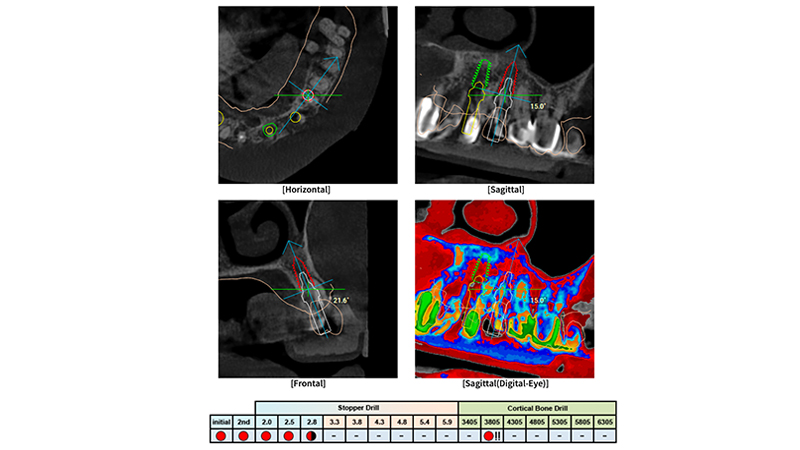

La riabilitazione si riferisce a una classe IV di Kennedy, in cui sette elementi dentari sono stati sostituiti grazie all'impiego di quattro fixtures. La loro posizione è stata pianificata utilizzando il software R2Gate® e sfruttando l’uso del tool “Digital Eye". Quest’ultimo consente di valutare la densità ossea durante la pianificazione del caso in modo digitale e fornisce una sequenza individualizzata di frese osteotomiche sito per sito.

La peculiarità di questo sistema è che le guide chirurgiche sono sprovviste di boccole (sleeveless) e sono stampate interamente in resina. Questa è la principale differenza rispetto ad altre sistematiche implantari oggi presenti sul mercato. Inoltre, le guide R2Gate® sono caratterizzate dalla metodica keyless, ossia non è prevista la presenza di alcuno stop o riduttore. La logica alla base di questa metodologia senza boccole e senza riduttori/stop è quella di semplificare le procedure chirurgiche. Infatti, tutte le informazioni relative alla boccola, agli stop per la preparazione del sito osteotomico implantare e ai riduttori sono incluse nella sequenza di frese chirurgiche. Inoltre, il software di pianificazione digitale è dotato di uno strumento chiamato “Digital Eye” che consente di valutare in anticipo la densità ossea in ciascun sito implantare. Su questa base, il chirurgo può modulare la sequenza di fresatura per raggiungere la stabilità primaria in base alla posizione dell'impianto e ai volumi di tessuto disponibili [4-5]. L'obiettivo del presente case report è illustrare la risoluzione di un caso clinico mediante impianti Megagen Anyridge posizionati attraverso l'innovativa sistematica di chirurgia guidata R2Guide (Megagen implants, Daegu, Corea del Sud).

Si è proceduto quindi a pianificare mediante il software R2Gate® la posizione delle fixtures impiantati nei siti che sono stati ritenuti maggiormente favorevoli per poter garantire una stabilità primaria adeguata. Tale procedura è stata semplificata dall’analisi suggerita dal tool “Digital Eye” che ha inoltre suggerito la corretta sequenza di frese da utilizzare per ciascun impianto (Figs. 3, 4, 5).

Fig. 3 - Pianificazione chirurgica mediante R2Gate®

Fig. 4 - Pianificazione chirurgica associata a Digital Eye, sequenza di frese individualizzata per ciascun sito implantare